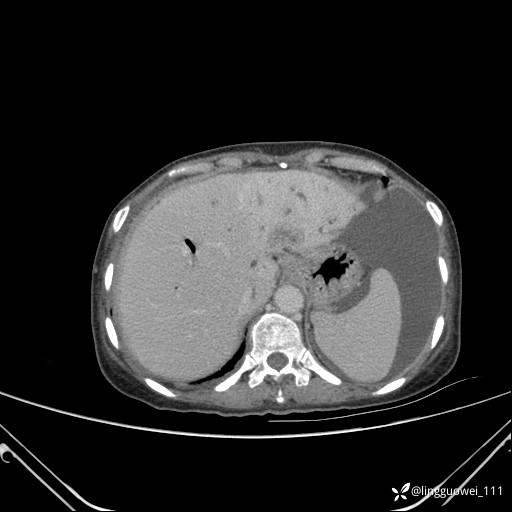

病例女,65岁,门诊行胃肠镜检查后,说腹胀入院检查,CT能发现病因吗?已公布结果

患者性别:女

患者年龄:65岁

主诉:门诊行胃肠镜检查后,诉腹胀,入院检查,肝有病变吗?腹膜及腹腔的表现有特征性吗?

平扫: